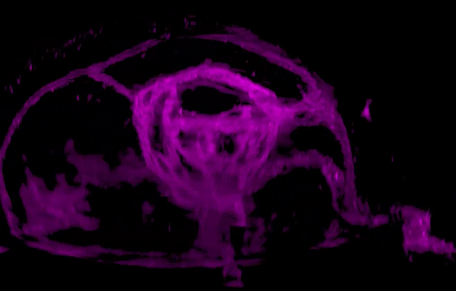

研究人員發(fā)現(xiàn),視網(wǎng)膜干細(xì)胞只能由視泡中間上皮細(xì)胞中一群雙潛能細(xì)胞產(chǎn)生,這群雙潛能細(xì)胞產(chǎn)生視網(wǎng)膜干細(xì)胞的同時(shí)產(chǎn)生視網(wǎng)膜色素細(xì)胞。為深入研究視網(wǎng)膜干細(xì)胞發(fā)育的分子機(jī)制提供了細(xì)胞譜系基礎(chǔ),為最終理解視網(wǎng)膜干細(xì)胞的產(chǎn)生和維持機(jī)制提供可能。

2017年7月26日,西雅圖華盛頓醫(yī)學(xué)院大學(xué)的科學(xué)家們在《Nature》上發(fā)表名為“Stimulation of functional neuronal regeneration from Müller glia in adult mice”的論文,在小鼠的眼睛中再生了視網(wǎng)膜細(xì)胞。

雖然小鼠與人類是不同的生物,但是,和人類一樣,小鼠對(duì)于視網(wǎng)膜的損傷也是束手無策的。然而世間萬物總是有一些特別的生物的存在,就像斑馬魚,其視網(wǎng)膜中含有的Müllerglia細(xì)胞攜帶一種能讓它們再生的基因——Ascl1基因,在視網(wǎng)膜受損后,該基因會(huì)被激活進(jìn)行修復(fù)。

科學(xué)家們通過實(shí)驗(yàn),在成年小鼠眼中再生出了功能正常的視網(wǎng)膜細(xì)胞,這對(duì)于人類視網(wǎng)膜細(xì)胞再生研究十分重要。研究人員表示,他們希望找到其他可以被激活的因子,以使Müllerglia細(xì)胞能再生出所有的視網(wǎng)膜細(xì)胞,這樣就有可能開發(fā)出修復(fù)視網(wǎng)膜損傷的治療方法,讓那些因視網(wǎng)膜受損而失去視力的人重見光明。